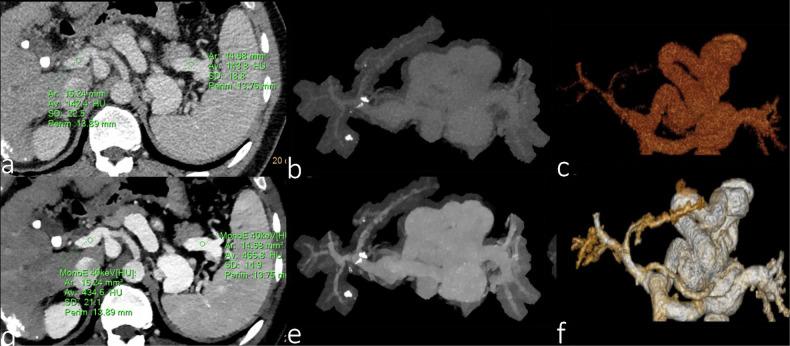

DLCT consists of a top layer sensitive to lower-energy photons and a bottom layer sensitive to higher-energy photons. This configuration enables simultaneous acquisition of two energy spectra from a single X-ray beam ensuring consistent spatial alignment and temporal resolution. Spectral raw images allow image post-processing to improve image quality, reduce radiation doses and contrast media doses, and generate multiple quantitative parameters. It has broad potential for early detection, accurate staging, efficacy assessment, and prognosis prediction of liver, pancreatic, and gastrointestinal diseases, as well as for the assessment of digestive system vasculature.

DLCT由对低能光子敏感的顶层和对高能光子敏感的底层组成。这种配置能够从单个X射线束同时采集两个能谱,确保空间对准和时间分辨率一致。光谱原始图像允许进行图像后处理,以提高图像质量、降低辐射剂量和造影剂剂量,并生成多个定量参数。它在肝脏、胰腺和胃肠道疾病的早期检测、准确分期、疗效评估和预后预测以及消化系统血管评估方面具有广阔的潜力。